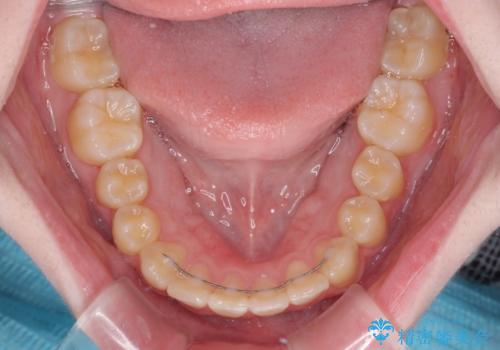

治療途中で大学受験があり、来院できない時期がありましたが、2年以内で満足のいく歯並びを達成することができました。